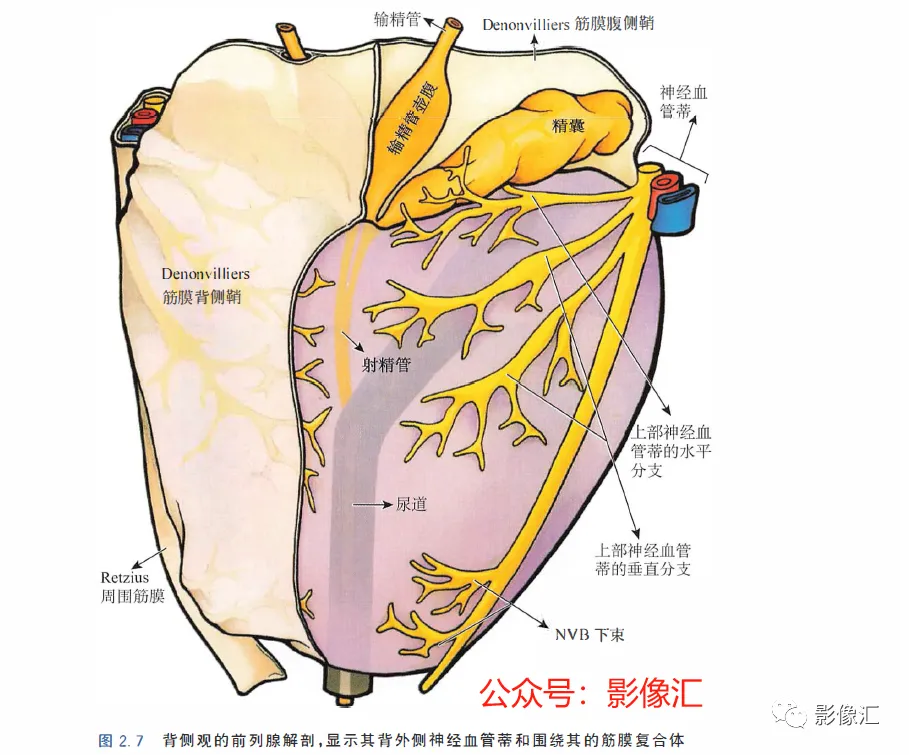

McNeal解剖模型认为前列腺根据周围不同结构环绕的关系而分为四个区域。尿道是描述整个前列腺区域解剖结构的解剖学标志。尿道由近端和远端尿道两个部分组成,每个部分约15mm长,由精阜分界。在精阜处,近端和远端尿道的走行呈35°。尿道壁由纵向走行的平滑肌纤维组成。围绕该内层的纵向肌肉层,是一层环形走行的肌层。两层平滑肌构成所谓的尿道内括约肌(IUS),其从膀胱颈延伸到尿道膜部的末端。IUS在膀胱颈的近端水平处最厚,随其向尿道膜部延伸,厚度逐渐减小。尿道膜部完整地被IUS环绕。在其前侧,前列腺内的lUS与前列腺肌性间质(AFMS)融合。两射精管走行方向与远端尿道平面平行,其开口于尿道腔内的前列腺小囊。移行带在前列腺组织中约占5%,构成两叶分别位于近端尿道两侧。其导管系统平行于尿道平面走行,止于精阜,射精管开口的近侧。移行带毗邻外周带,中央带和前列腺肌性间质,构成所谓的外科手术包膜,也就是说,确定了前列腺剜除术的外科手术平面。移行带和尿道周围腺体组织是良性前列腺增生(BPH)的发生部位。前列腺癌发生在移行带的比例为10%~20%。中央带在前列腺腺体组织中约占25%。其在前列腺底部形成金字塔形或锥形结构,在精阜水平处变窄至顶点。中央带的导管在射精管开口的两侧呈放射状走行。精囊和输精管穿入中央带形成射精管形似“精囊喙”。此区域由于缺乏前列腺包膜而成为解剖薄弱区。与射精管延续的中央带及伴行的筋膜和淋巴血管组织称为前列腺嵌入部(invaginated extraprostatic space,IES)。这是另一个解剖学上的薄弱区域,因此中央带疾病容易沿此区域播散。中央带相对发病率较低,发生在中央带的前列腺癌占5%~10%。外周带和中央带之间缺乏解剖学屏障,同时由于IES的存在,意味着前列腺尖部发生的肿瘤很容易进展到前列腺底部,并可早期造成前列腺周围间隙结构的受累。外周带约占前列腺腺体组织的70%。其包括前列腺表面的外侧、背侧和尖部,以多变的方式向腹侧延伸,与前纤维肌性间质相延续。前列腺不具有通常意义上的包膜结构,表面有一层腺样间质被称为“包膜"。前列腺“包膜”本身由纤维肌性间质构成,其在腺体周围形成一薄层结构。前列腺尖部没有这种间质层,造成一个解剖学上的蒲弱区域,称为梯形区域(trapezoidal area)。该区域腹侧以尿道膜部为界,背侧则以Denonvilliers和直肠筋膜为界,头侧以前列腺尖部(外周带)为界,尾侧则以直肠尿道肌为界。70%的前列腺癌发生在前列腺外周带。当前列腺癌起自前列腺尖部时,在早期即可通过梯形区域侵犯前列腺周围间隙。前列腺的背外侧神经血管蒂也是肿瘤易向外蔓延和侵袭的区域。AFMS约占前列腺体积的33%,是前列腺的非腺体区域,构成前列腺的前表面。在其最近端部分,其与逼尿肌和尿道内括约肌(IUS)的平滑肌纤维融合。头侧,其保持和尿道外括约肌(EUS)的关系;EUS的横纹肌纤维在该区域(前列腺尖部的前外侧)融合,构成前列腺外括约肌群。有四个“解剖薄弱“ 区域,通过这些区域,前列腺肿瘤可以生长并侵犯相邻的结构。这些区域是:精囊喙(图2. 6和图2. 17)

前列腺蒂周围间隙(图2.7和图2. 17)

在盆腔侧壁和下壁肌肉骨髂层与前壁层腹膜隐窝之间头侧存在“腹膜下盆腔间隙”,该间隙中线处为盆腔内脏,两侧面为神经血管蒂。该间隙同时含有丰富的纤维脂肪组织,在头侧与腹膜外脂肪组织相延续,侧方通过坐骨切迹与臀部及会阴部的脂肪组织相延续。腹膜下盆腔间隙中不同的细胞-纤维鞘分隔,分隔并不完整,这些细胞-纤维鞘起自盆腔血管的血管鞘,并与血管伴行,从其起源的盆腔侧壁走行至所相应供血的内脏区域。这些细胞-纤维鞘也被称为“血管隔膜”。其由纤维结缔组织、弹性纤维、脂肪组织和平滑肌纤维组成。很重要的是要知道位于盆腔内部的这些筋膜的分布,该筋膜内存在着盆腔脏器所有的供血血管及神经支配,并形成根治性前列腺切除术中采用的不同手术分离平面。

AFMS:前列腺肌性间质;CZ:中央带;PZ:外周带;SV:精囊;IUS尿道内括约肌。两个矢状面走行筋膜:Farabeuf骶骨-直肠-生殖-膀胱-耻骨鞘(左右各一);三个横轴面走行筋膜:脐-膀胱前筋膜;“生殖动脉隔”;直肠中动脉的隔(Septum of the mid-hae-morrhoiclal artery)。在前列腺,这些鞘也被称为“Retzius前列腺周围筋膜”“前列腺周围筋膜”“前列腺侧带”,或者最近称为“盆内筋膜腹侧面” 。这些筋膜覆盖腺体的侧面和腹侧,在腹侧与前纤维肌性间质(AFMS)融合。供血血管和支配神经在这些鞘内走行。一旦解剖前列腺后部或直肠前平面,这些鞘在前列腺的两侧形成手术分离平面。前列腺“本身”不具有包膜结构;所谓的包膜只是腺样间质聚集所致,而且个体间变异度很大,同时在某些点上并不存在,从而构成McNeal所述的解剖薄弱区域。因此,从实际的角度来看,我们认为虽然前列腺没有自己的包膜结构,但其确实有三个“假包膜":